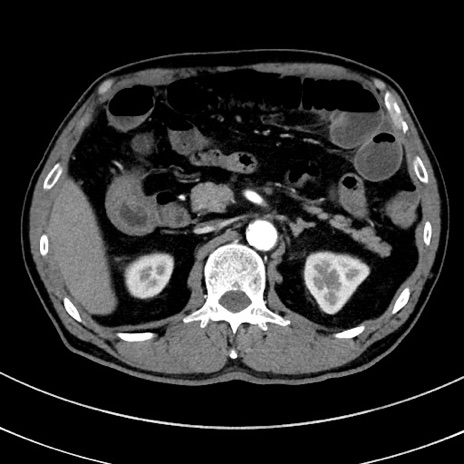

症例8(横断像)

【症例】 60歳代男性

【主訴】 黒色吐物

【現病歴】 4日前から嘔気自覚、2日前の朝食後にも嘔気あり、自分で手で嘔吐反射起こし嘔吐したところ血が混ざっていたため受診。

【既往歴】 5年前汎発性腹膜炎を伴う急性虫垂炎で手術、高血圧、前立腺肥大症、高脂血症

【身体所見】 腹部正中に手術癩痕あり 腹部平坦・軟圧痛なし膨満感あり

【データ】WBC 8400、CRP 4.54